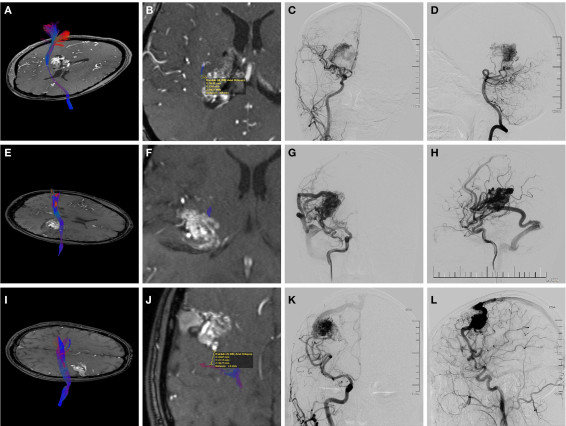

图2. 3例AVM患者术前MRA与DTI重建的皮质脊髓束融合图像以及DSA图像。A-D图.女性,38岁,入院前2次脑室出血;A、B图.MRA轴位图像示位于右额深部脑室旁AVM,侵犯内囊,融合影像显示畸形血管团与CST的最短距离为2.0mm,最接近CST水平位于内囊后肢;C、D图.右侧颈内动脉的前后位和侧位DSA图像示弥漫型畸形血管团,伴有深静脉引流;supp S-M分级为7级,CLAD量表分级为5级;术后,患者发生永久性左侧肢体肌力减退,最后随访时左侧肢体肌力为3-4级。E-H图.男性,21岁,因颞叶出血入院;E、F图.MRA轴位图像示AVM位于右侧裂区深部,侵犯内囊后肢,畸形血管团与CST的最短距离为0mm,最接近CST水平位于内囊后肢;G、H图.右侧颈内动脉的前后位和侧位DSA图像显示密集型畸形血管团,浅表静脉引流;supp S-M分级为5级,CLAD量表分级为5级;术后,永久性左侧肢体肌力减退,最后随访时左侧肢体肌力为4级。I-L图.男性,29岁,因癫痫发作入院;I、J图.MRA轴位图像示AVM靠近右中央前回,融合影像显示畸形血管团与CST的最短距离为7.9mm,最接近CST水平位于大脑皮质或半卵圆中心;K、L图.右侧颈内动脉的前后位和侧位DSA图像示AVM浅表、向深部弥漫,由浅静脉引流;supp S-M分级为7级,CLAD量表分级为3级;术后,患者恢复良好。